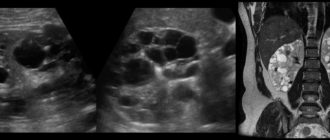

Причины возникновения, симптомы и лечение кисты почки 11.02.2018 3.2 тыс. 2.2 тыс. 5 мин.